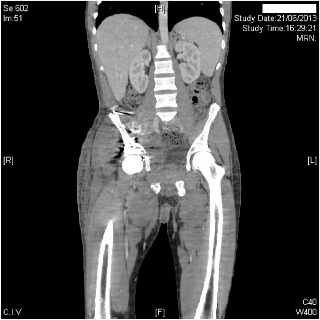

En este caso, lo importante es recordar que el problema no se trata del antibiótico (teniendo hemocultivos con antibiograma que muestran sensibilidad al mismo) sino de localización. Es poco probable que un cambio de antibiótico resuelva el problema de las colecciones en este paciente a no ser que se drenen.

El fracaso terapéutico en el tratamiento de una infección puede deberse a un foco no drenado al que el antibiótico no llega correctamente como era nuestro caso.